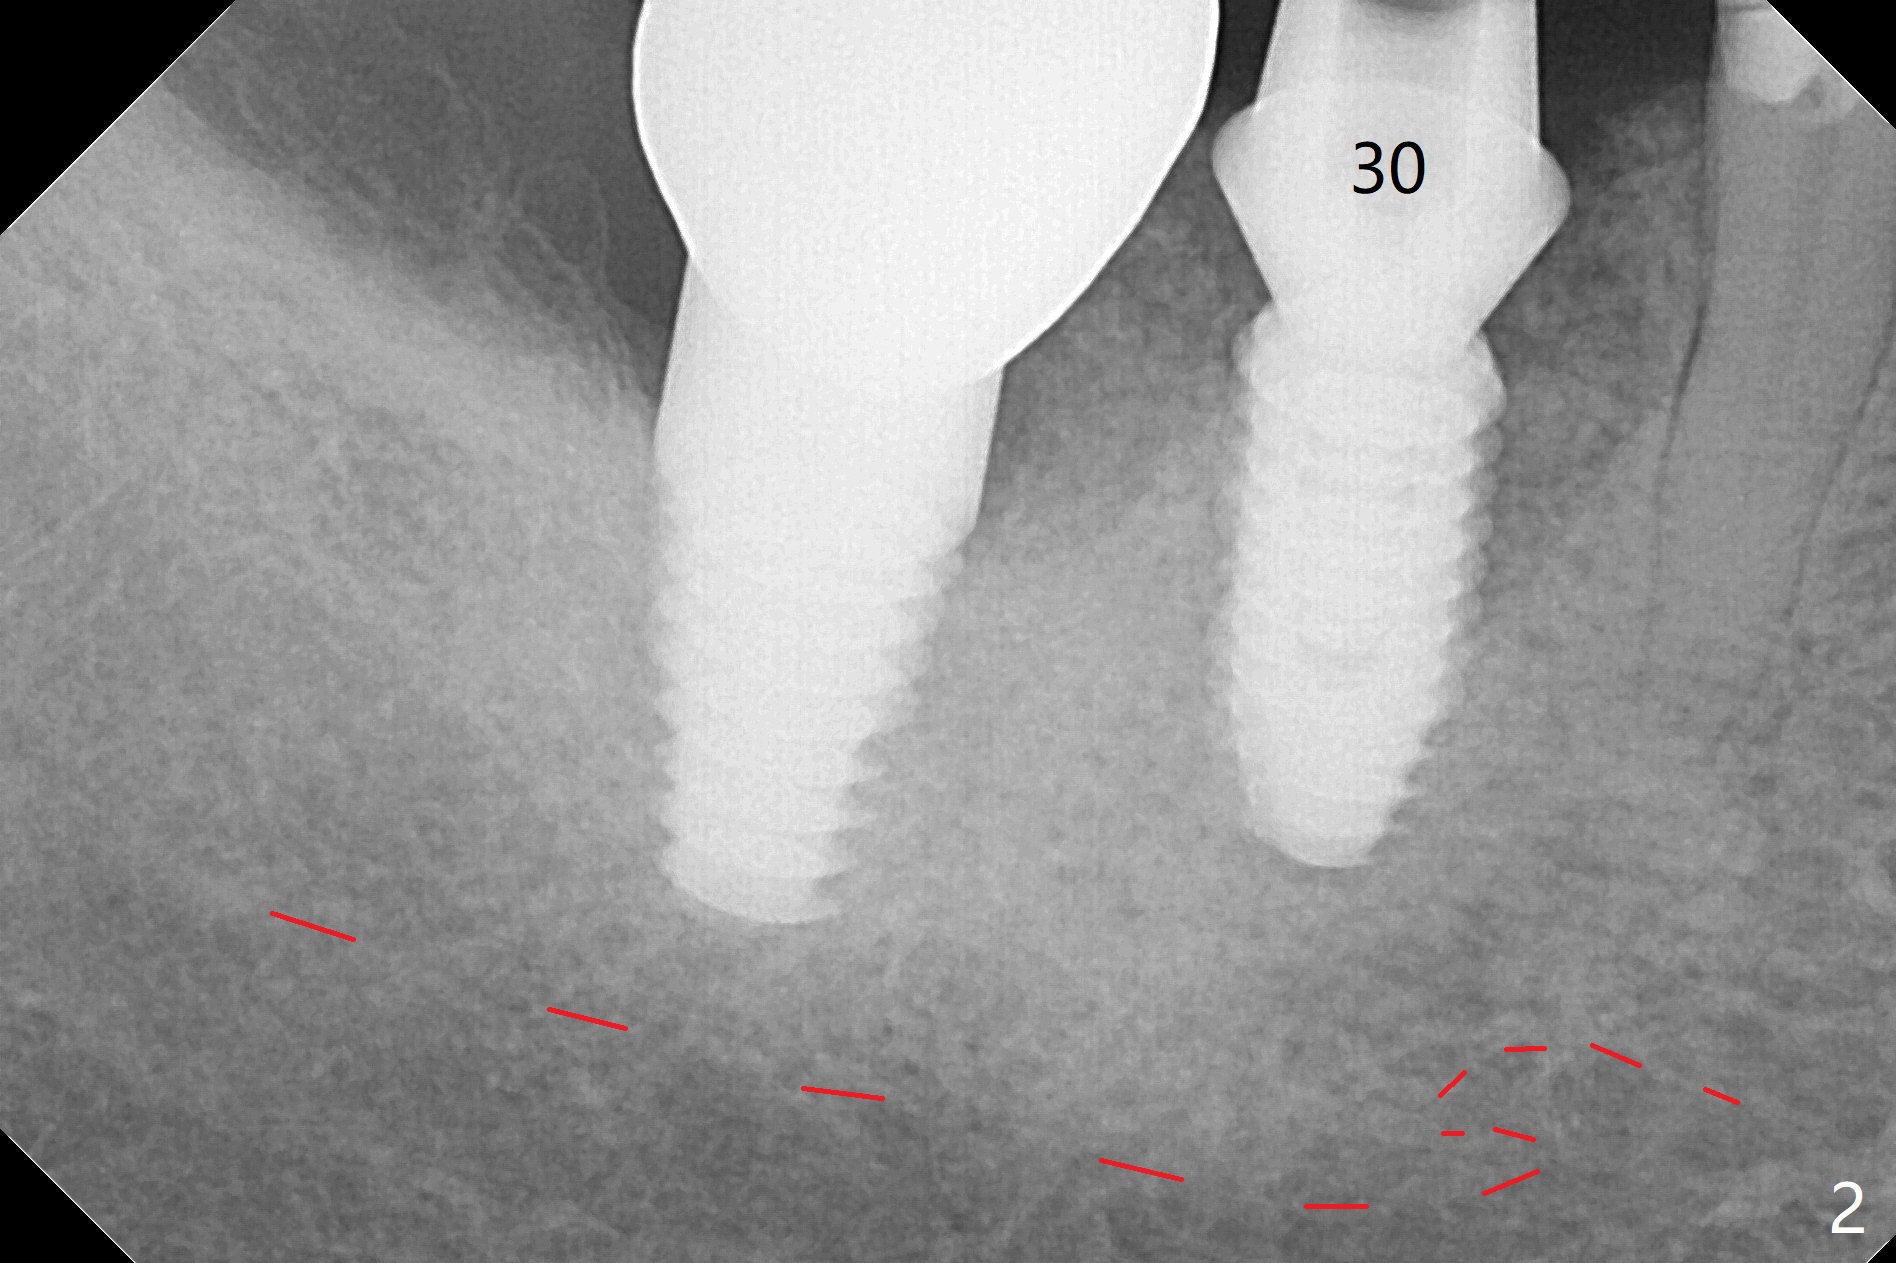

As compared to guided delayed implant placement, the immediate one in the 1st molar needs one more Lidocaine and one Septocaine for pain control. Trajectory is as good as expected with >50 Ncm (Fig.1,2 (red dashed line: superior border of the Inferior Alveolar Canal)). With insertion of Vanilla allograft with autogenous bone (Fig.1 *) and a 6.5x4(3) mm cementation abutment, an immediate provisional (Fig.3 P) is fabricated to keep the graft in place.